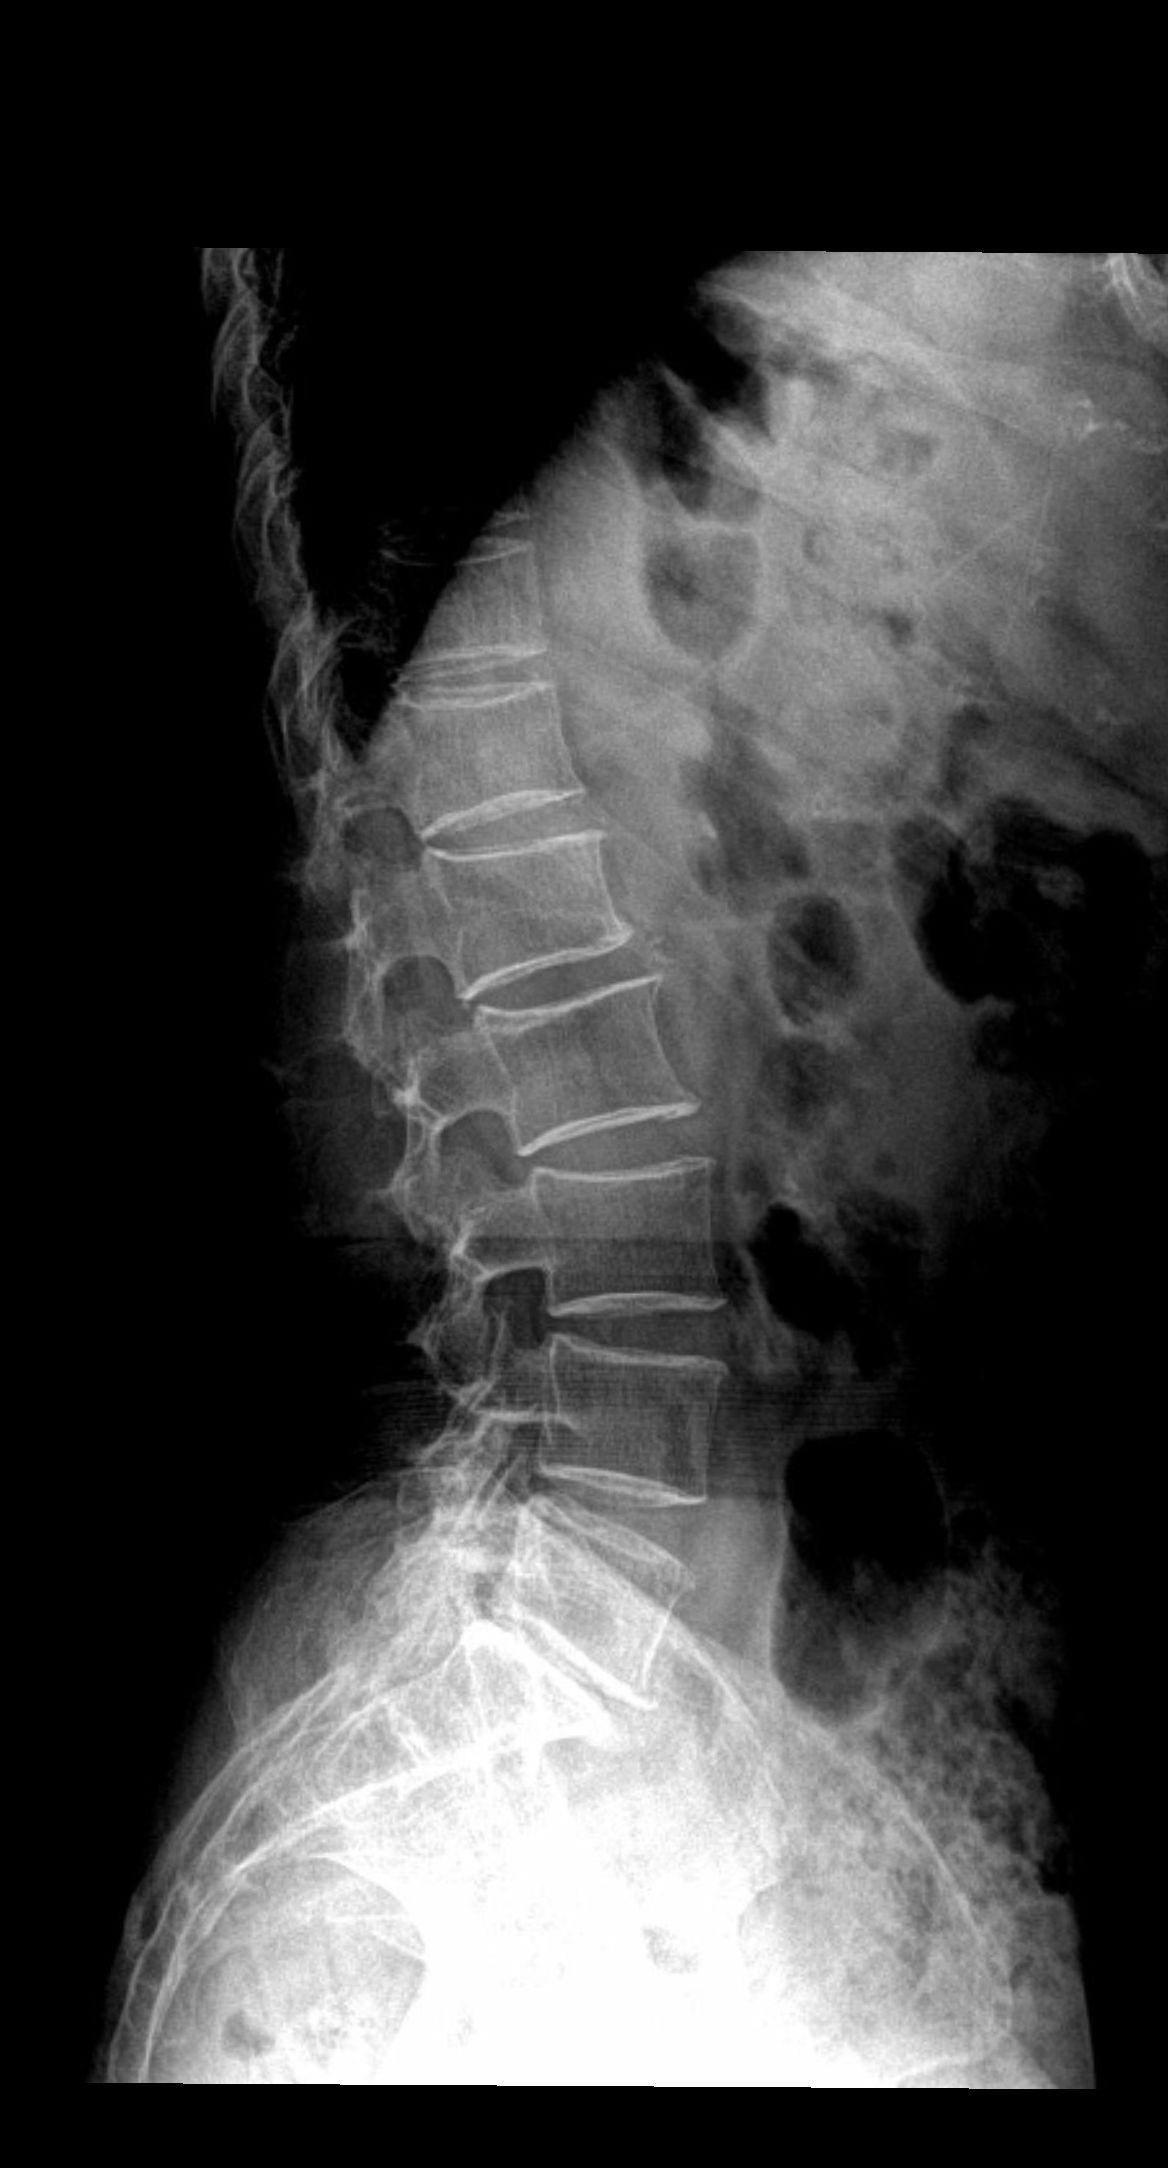

腰椎疼痛,下肢麻木酸疼

腰椎间盘突出好可怕!下肢麻木发冷太痛苦!腰椎退行性病变好难治!